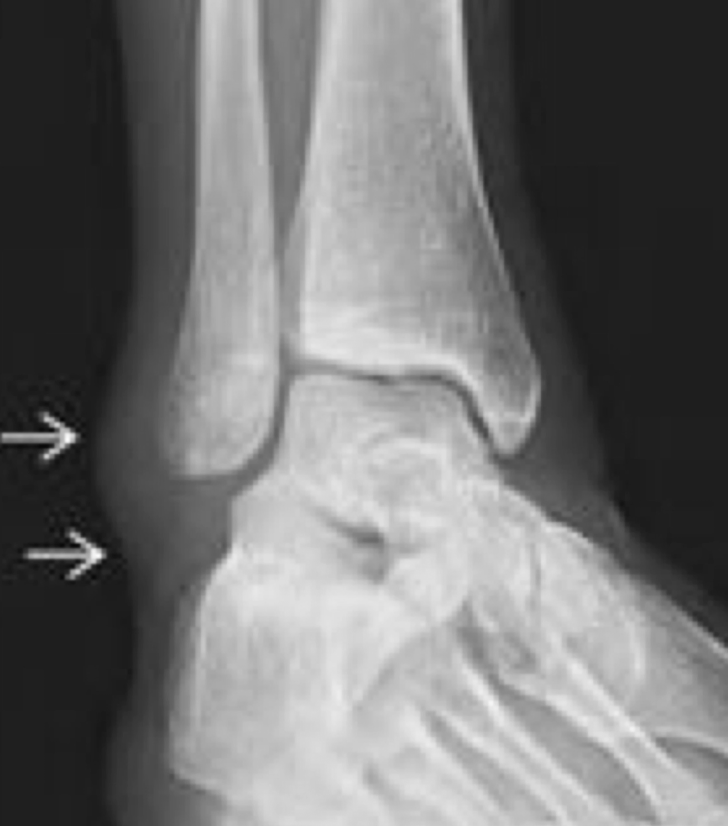

RX ESG

A

NO ve el lig: SI datos secund

- Edema tx blandos

- aumento del espacio entre peroné y ástragalo

Rx con estrés “bostezo”

- Descartar fx

TC usualmente para buscar fracturas